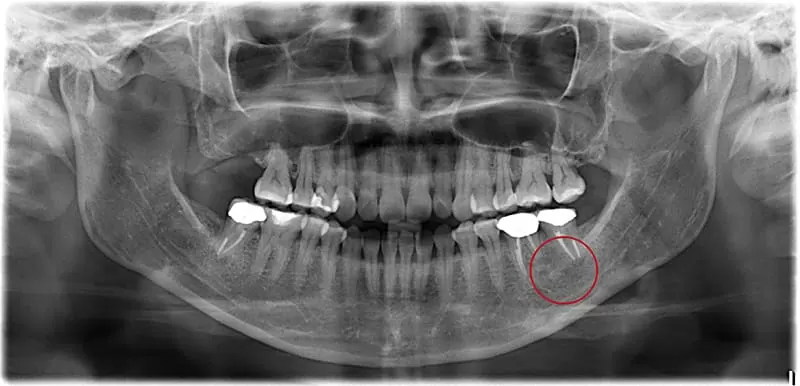

(1) 全口X光片

經由根管清創以及置放根管藥物,數次約診後,以顯微鏡確診病灶已無異常滲出物,則加以根管充填。給予臨時假牙配戴並追蹤兩年後,病灶在無手術介入的狀況之下完全消失,且齒槽骨再生,於是製作正式假牙後完成治療。